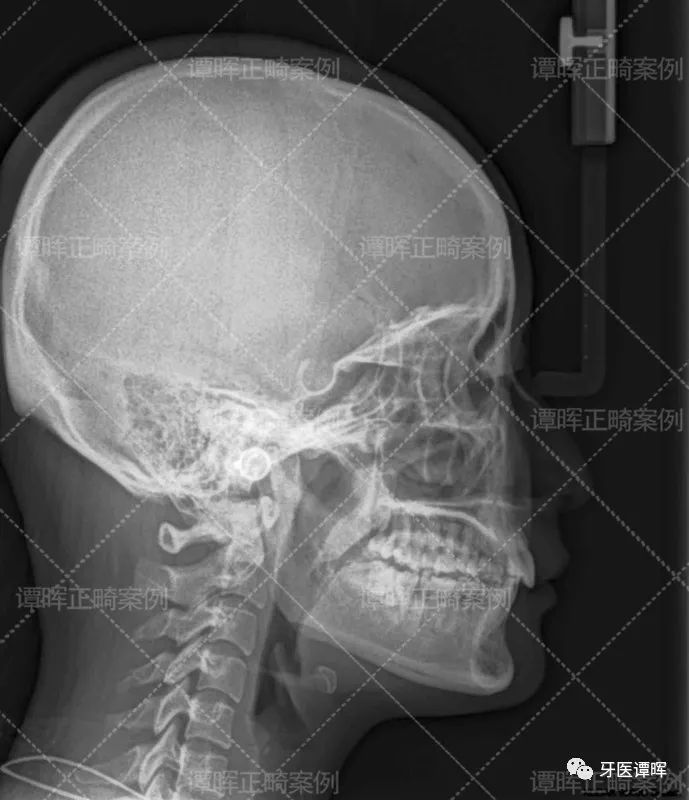

△X线分析:明显看出前牙往前突,上牙的侧切牙也是非常不齐。

从X线分析图可以明显看出前牙往前突内收,上牙的侧切牙也已排齐,牙列排齐。